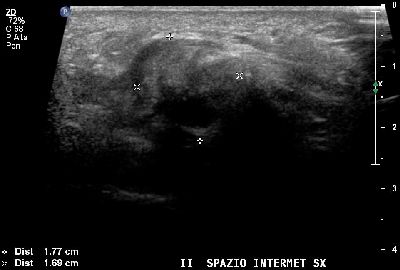

Neuroma di Hauser del secondo spazio intermetatarsale (img. 01) Neuroma Hauser 01